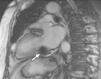

Case reportAn 84-year-old woman, with a history of hypertension and dyslipidemia, was admitted to our institution because of an intracardiac mass. She described a five-month history of shortness of breath on exertion (NYHA functional class III) and peripheral edema. Physical examination revealed a grade III/VI mitral systolic murmur. The electrocardiogram was unremarkable. Laboratory tests results showed no significant alterations. The transthoracic echocardiogram demonstrated a large, round, heterogeneous, echodense mass at the base of the posterior leaflet (Fig. 1). Doppler examination documented severe mitral regurgitation. The three-dimensional transthoracic echocardiogram revealed the mass involving the posterior mitral annulus, distorting it into a more triangular shape (Fig. 2). Three-dimensional transthoracic color flow imaging showed an eccentric mitral regurgitation jet originating from the posteromedial commissure (Fig. 3). The transesophageal echocardiogram confirmed the location of the mass and severe mitral regurgitation (Fig. 4), with two jets identified, one central and the other eccentric, apparently originating from the posteromedial commissure. Cardiac magnetic resonance (CMR) imaging was performed to better evaluate the mass. This showed a hypointense mass in the posterior region of the mitral annulus/basal segment of the inferior wall (Figs. 5 and 6). Rest perfusion CMR demonstrated hypoperfusion of the mass compared to normal myocardium (Fig. 7). Phase-sensitive inversion-recovery CMR showed late gadolinium enhancement in the peripheral margin of the mass (Fig. 8). On the basis of the above findings, a presumptive diagnosis of a centrally liquefied mass containing a high-protein or hemorrhagic content with an inflammatory and/or fibrotic wall was made. A multislice computed tomography (CT) scan of the heart was also performed, demonstrating a relatively homogeneous, high-density mass with foci of calcification (Figs. 9 and 10). A multi-modality imaging approach confirmed the diagnosis of caseous calcification of the posterior mitral annulus.